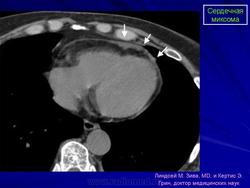

Миксома предсердия

ID: 8544 Atrial myxoma Dr Frank Gaillard - 10 Feb 2010 This patient went on to have a resection and an atrial myxoma was confir...

ID: 14404 Atrial myxoma on CTPA Dr Jeremy Jones - 21 Jul 2011 No PE or other cause of breathlessness on review of the lungs. How...